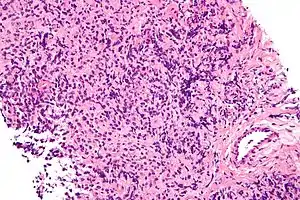

| Micrograph of a primary mediastinal large B-cell lymphoma, a type of large-cell lymphoma. H&E stain. | |